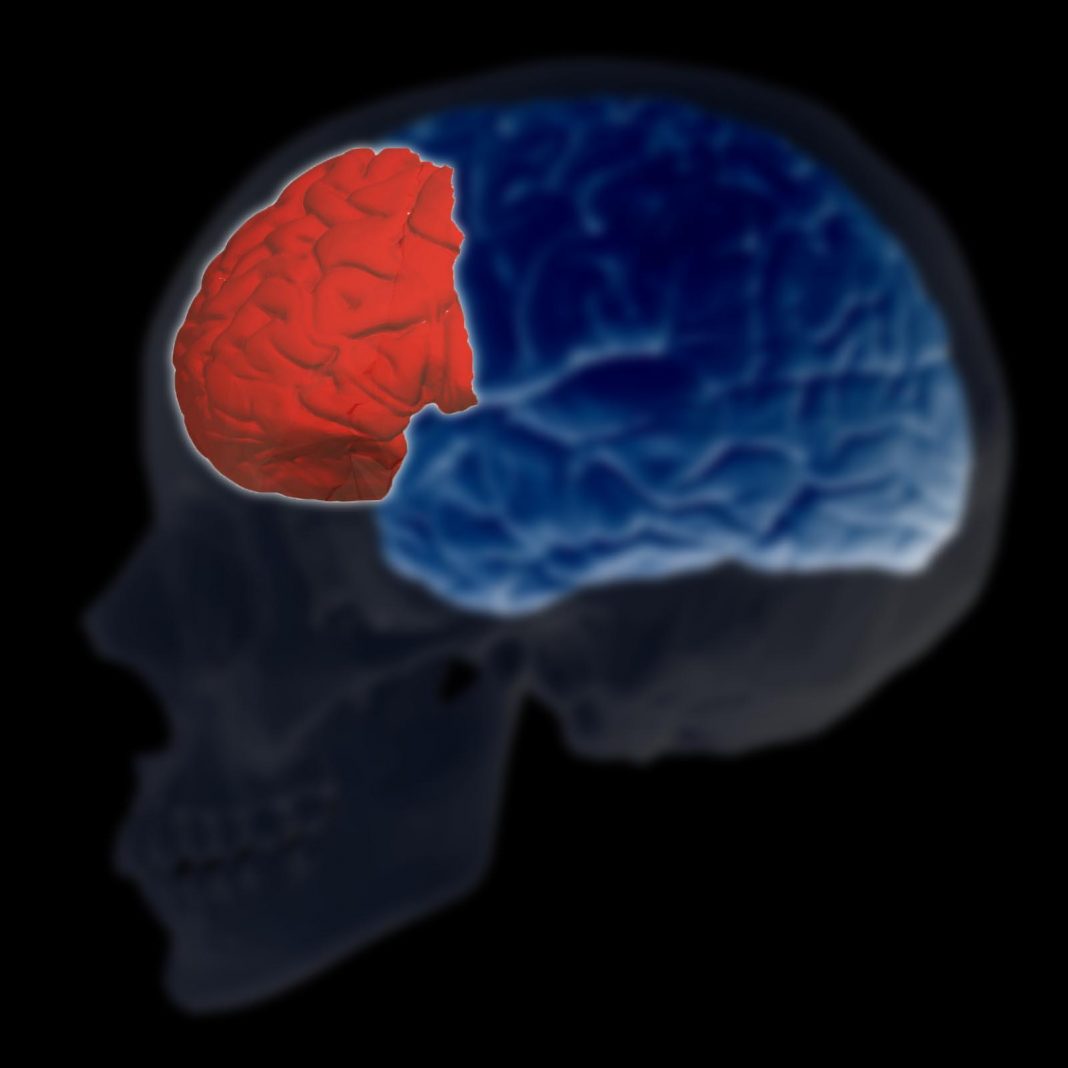

1Reducción de la corteza cerebral

Los daños que produce el tabaco a nivel cerebral son bastante graves. El 14% de los casos diagnosticados de demencia son causados por consumo de tabaco y casi el 15% de los tumores a causa del tabaquismo, se producen en algunas partes de la cabeza y el cuello.